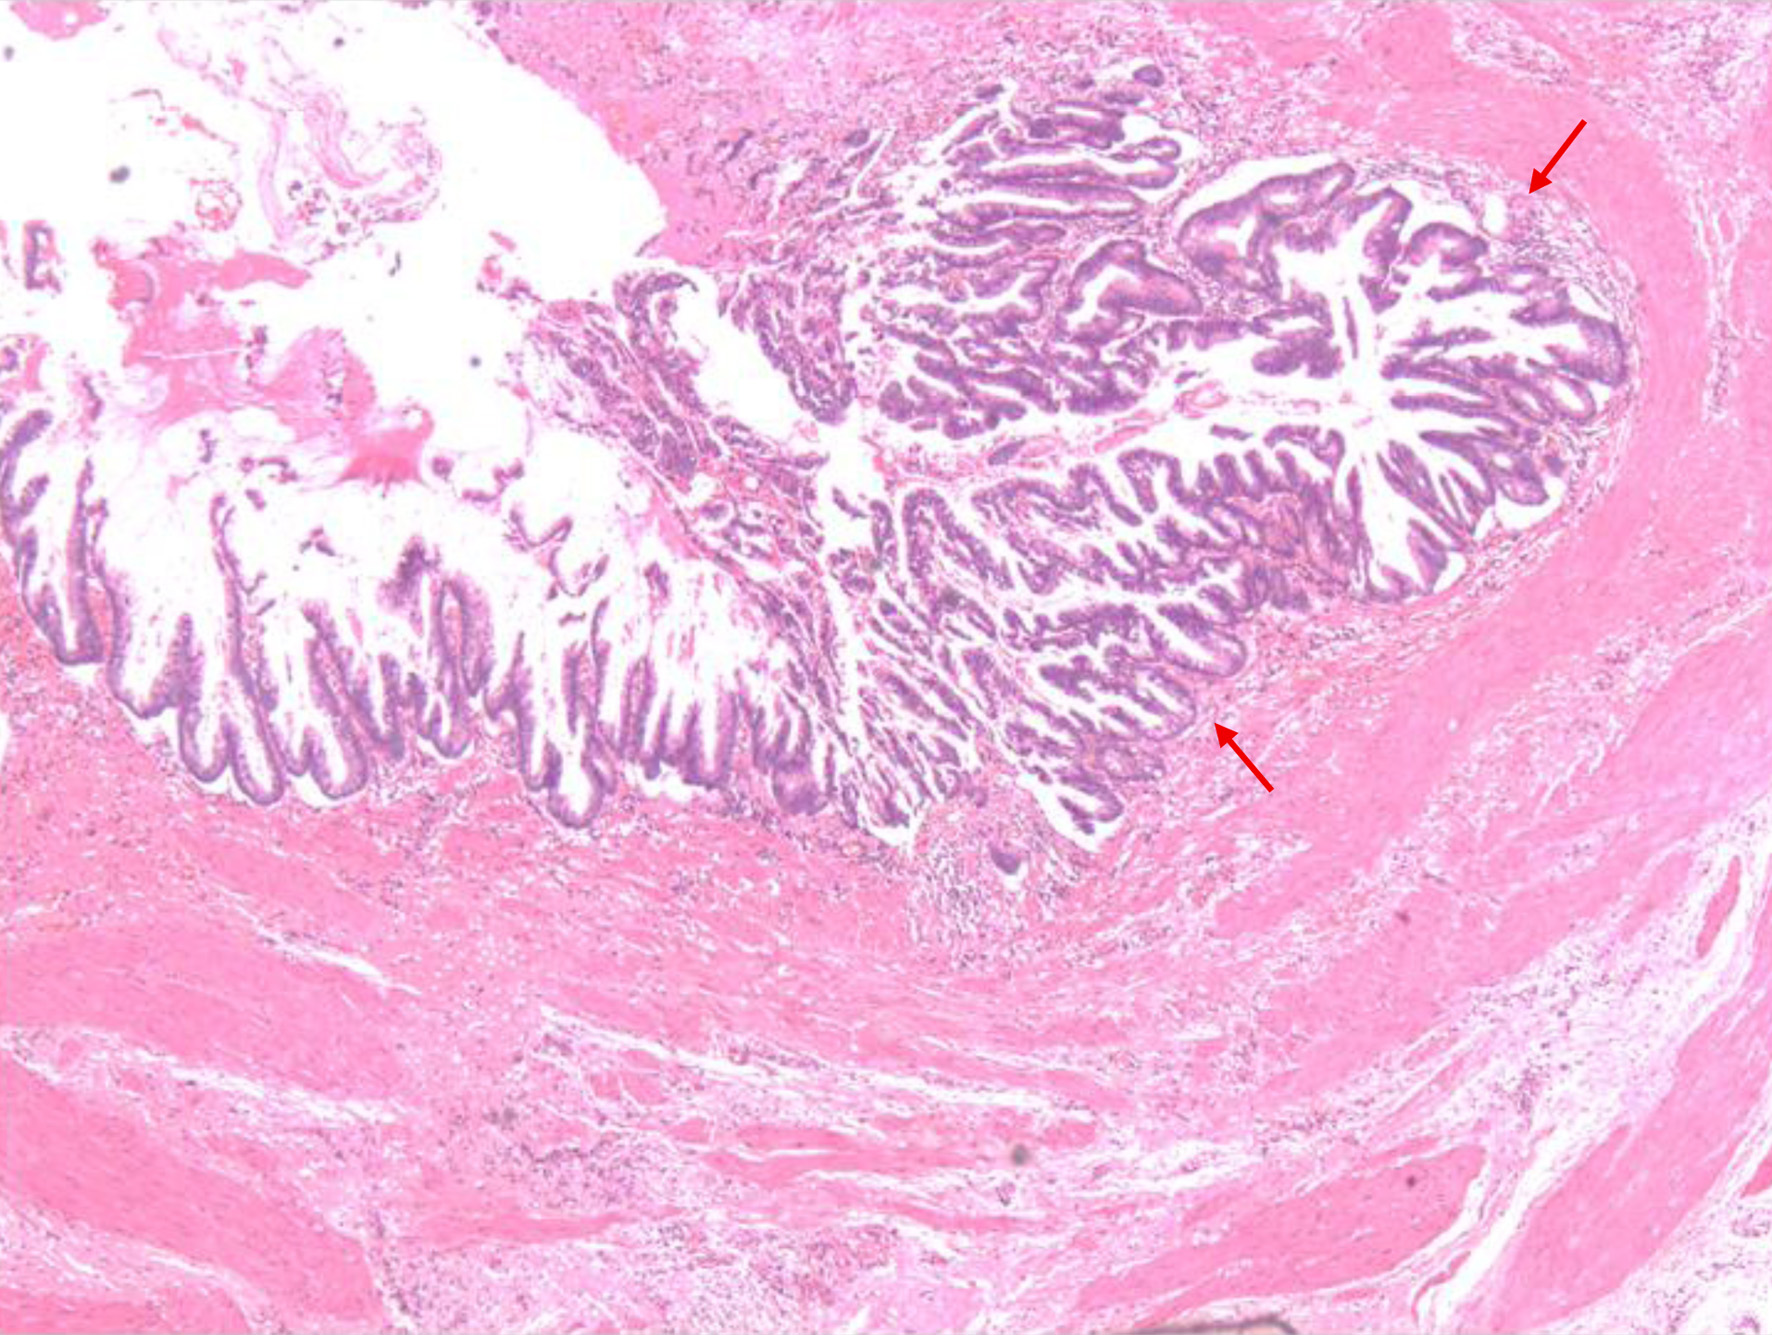

Postoperatively, the patient had an uneventful recovery. The drain and catheter were removed on the second postoperative day. The sinus tract was managed with daily dressings until it healed by secondary intention. Histopathology revealed villous adenoma of the ureter, with no evidence of high-grade dysplasia or malignancy. Similarly, histopathology of the ureteral stump confirmed villous adenoma without signs of high-grade dysplasia or malignancy. As shown in Figure 4, there were no high-grade nuclear features or significant mitotic activity, confirming the benign nature of the disease. The patient was followed up in the clinic after discharge and had no complaints or complications.

Figure 4. Histopathological section of the ureteric wall showing a lesion with papillary configuration, composed of fused tubules lined by columnar epithelium and goblet cells exhibiting pseudostratification and low-grade dysplasia (arrows). No evidence of muscularis or vascular invasion is identified.